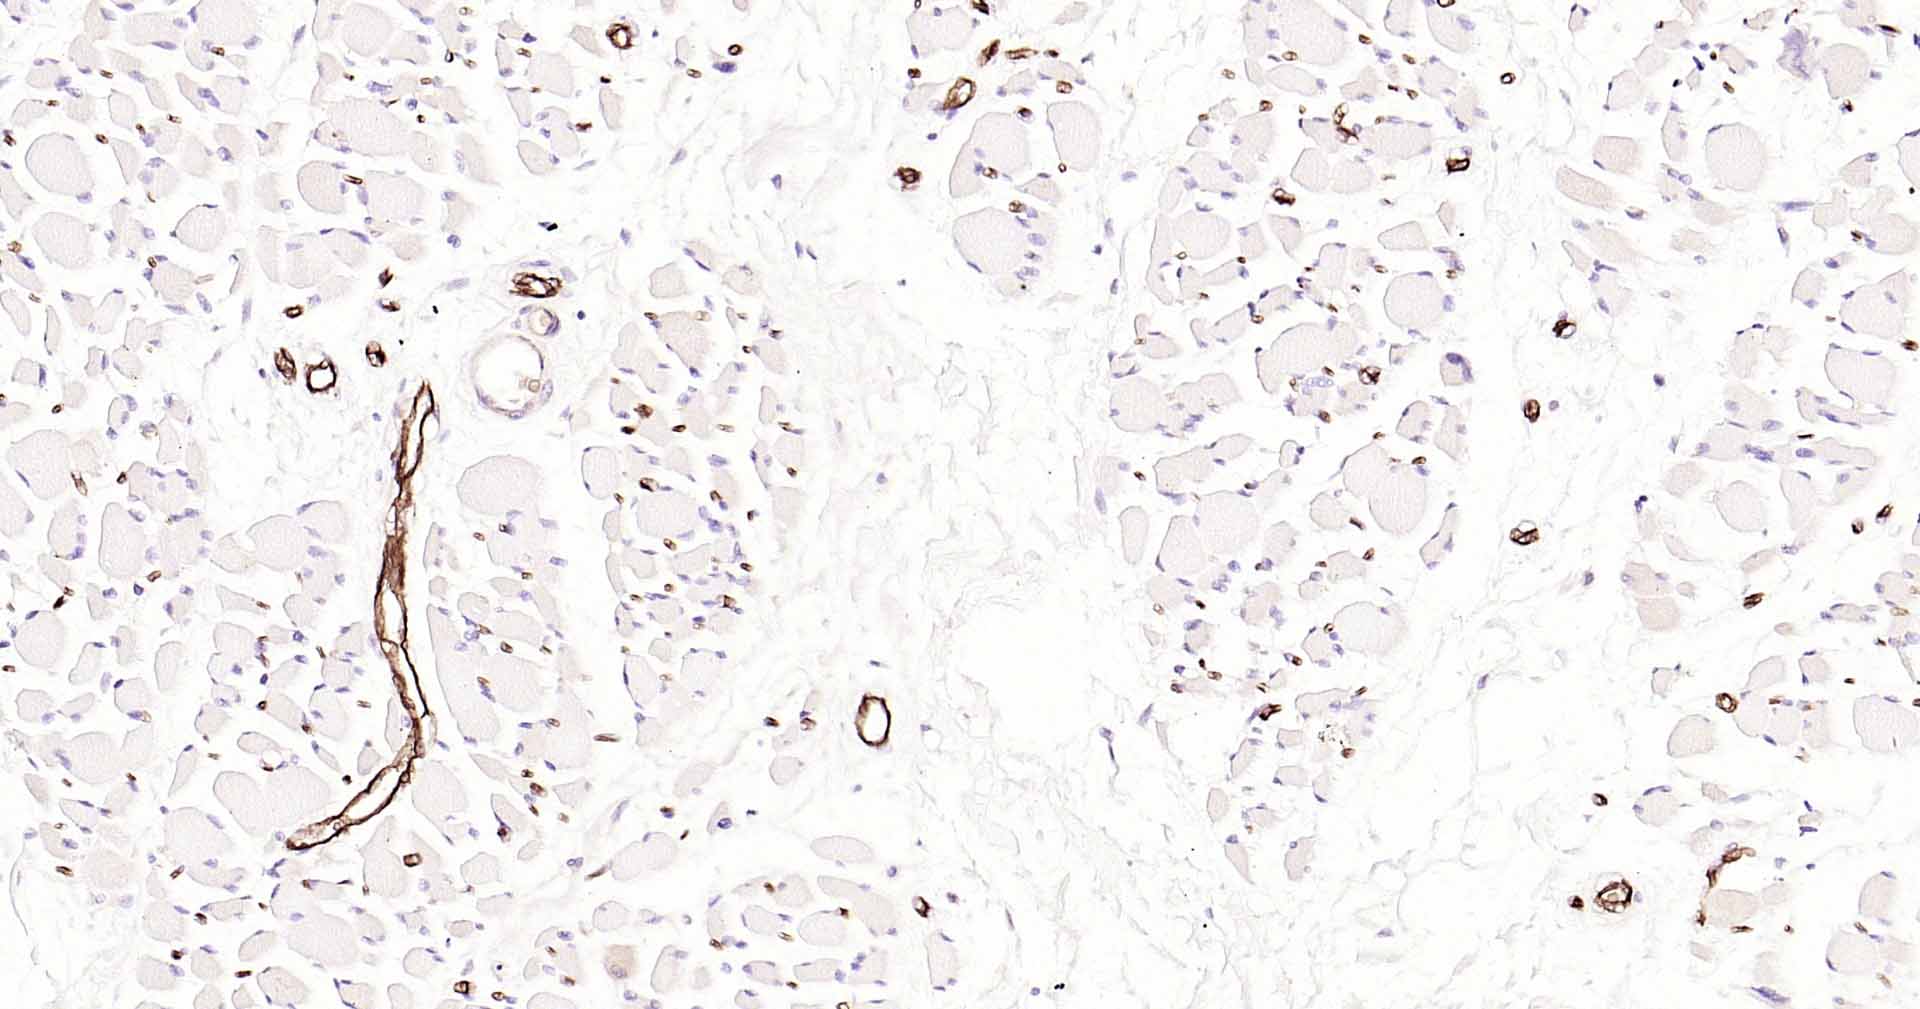

Paraformaldehyde-fixed, paraffin embedded Human Skeletal muscle; Antigen retrieval by boiling in sodium citrate buffer (pH6.0) for 15 min; Antibody incubation with AQP1 Monoclonal Antibody, Unconjugated(bsm-52909R) at 1:200 overnight at 4°C, followed by conjugation to the SP Kit(Rabbit, SP-0023) and DAB (C-0010) staining.

Paraformaldehyde-fixed, paraffin embedded Rat Skeletal muscle; Antigen retrieval by boiling in sodium citrate buffer (pH6.0) for 15 min; Antibody incubation with AQP1 Monoclonal Antibody, Unconjugated(bsm-52909R) at 1:200 overnight at 4°C, followed by conjugation to the SP Kit(Rabbit, SP-0023) and DAB (C-0010) staining.

Paraformaldehyde-fixed, paraffin embedded Mouse Skeletal muscle; Antigen retrieval by boiling in sodium citrate buffer (pH6.0) for 15 min; Antibody incubation with AQP1 Monoclonal Antibody, Unconjugated(bsm-52909R) at 1:200 overnight at 4°C, followed by conjugation to the SP Kit(Rabbit, SP-0023) and DAB (C-0010) staining.